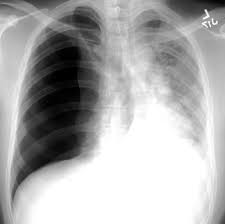

Chest X Ray Showing Large Right Pneumothorax With Collapsed Lung Download Scientific Diagram from www.researchgate.net Jul 02, 2021 · a collapsed lung occurs when air escapes from the lung. Air can enter the pleural space by two mechanisms, either. Now with integrated gestational age calculator and decision support (e.g., retinopathy of prematurity, rsv prophylaxis). Search only for pneumothorax x ray It occurs when air accumulates between the parietal and visceral pleurae inside the chest. The air accumulation can apply pressure on the lung and make it collapse. The degree of collapse determines the clinical presentation of pneumothorax. This buildup of air puts pressure on the lung, so it cannot expand

This buildup of air puts pressure on the lung, so it cannot expand pneumothorax. Nov 16, 2020 · a pneumothorax is defined as a collection of air outside the lung but within the pleural cavity.